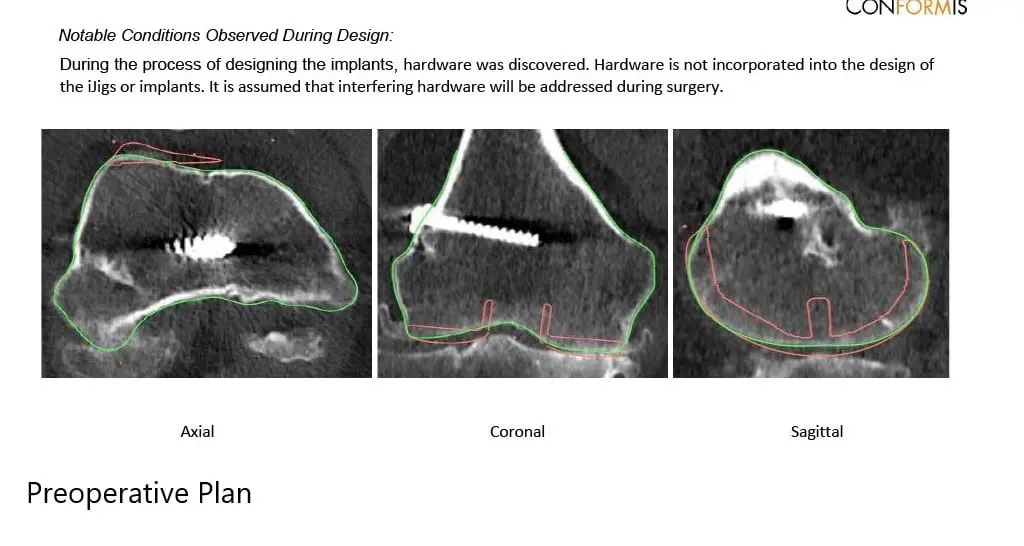

A preoperative CT scan obtained a few weeks prior to the procedure. The data was used to assess the patient’s unique anatomy and biomechanics. Customized unique patient-specific implants were made. Disposable bone cutting guides were 3D constructed to match the patient’s anatomy. A preoperative plan was formulated to guide the surgery.

Complete Orthopedics patient-specific surgical plan for a custom right total knee replacement in a 55-year-old female with Prior ACL Reconstruction.

Complete Orthopedics patient specific surgical plan for a custom right total knee replacement in a 55-year-old female with prior ACL Reconstruction (scan 2)